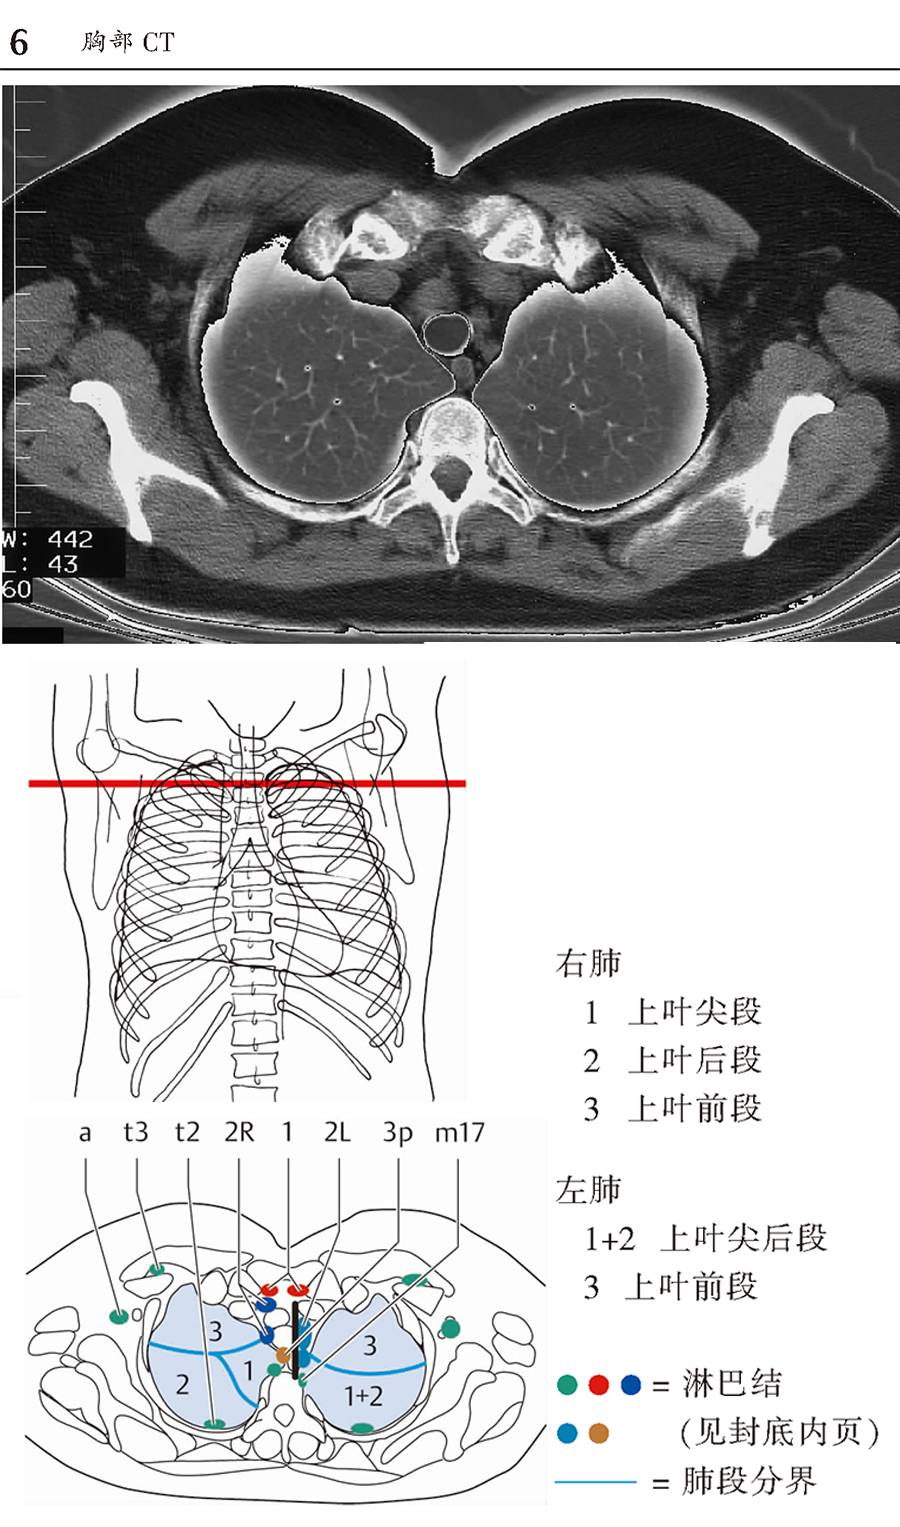

本书为断层解剖图谱,包括头颈部断层解剖,还包括脑部血管造影术,每一层面都包括精确的断层解剖和对应的彩色插图,左边页面为CT/MR图像,右边页面为对应的彩色手绘解剖示意图,便于学习和记忆!

1、版面采用教学式设计,2页为一个单元,左边页面为CT/MR图像,右边页面为对应的彩色手绘解剖示意图,并一一注明了解剖部位。

3、彩色手绘示意图中,各断层图像中同一个解剖结构均采用相同的颜色标注,便于识别。

书中全面、详细描述了每个CT/MR断层的解剖部位,图片清晰,浅显易懂,非常便于阅读和理解。书中每幅CT/MR图像都配有手绘的彩色示意图,示意图与影像图片高度匹配,通过示意图可以加深对CT/MR图像的理解,使CT/MR图像不再那么抽象难懂,同时也增加了学习的乐趣,不再感觉CT/MR图像的学习非常枯燥。本书内容全面、简洁易懂,是一本高质量的解剖图谱,非常适合影像诊断专业医师学习。

版面采用 教学式设计,2页为一个单元,左边页面为CT/MR图像,右边页面为对应的彩色手绘解剖示意图,并一一注明了解剖部位。

彩色手绘示意图中,各断层图像中同一个解剖结构均采用相同的颜色标注,便于识别。

l 胸部和腹部所有CT图像均为轴位、矢状位和冠状位三个层面图像。

l 封底折页内新增肺段、肝段和淋巴结分级。

胸部CT-横断面